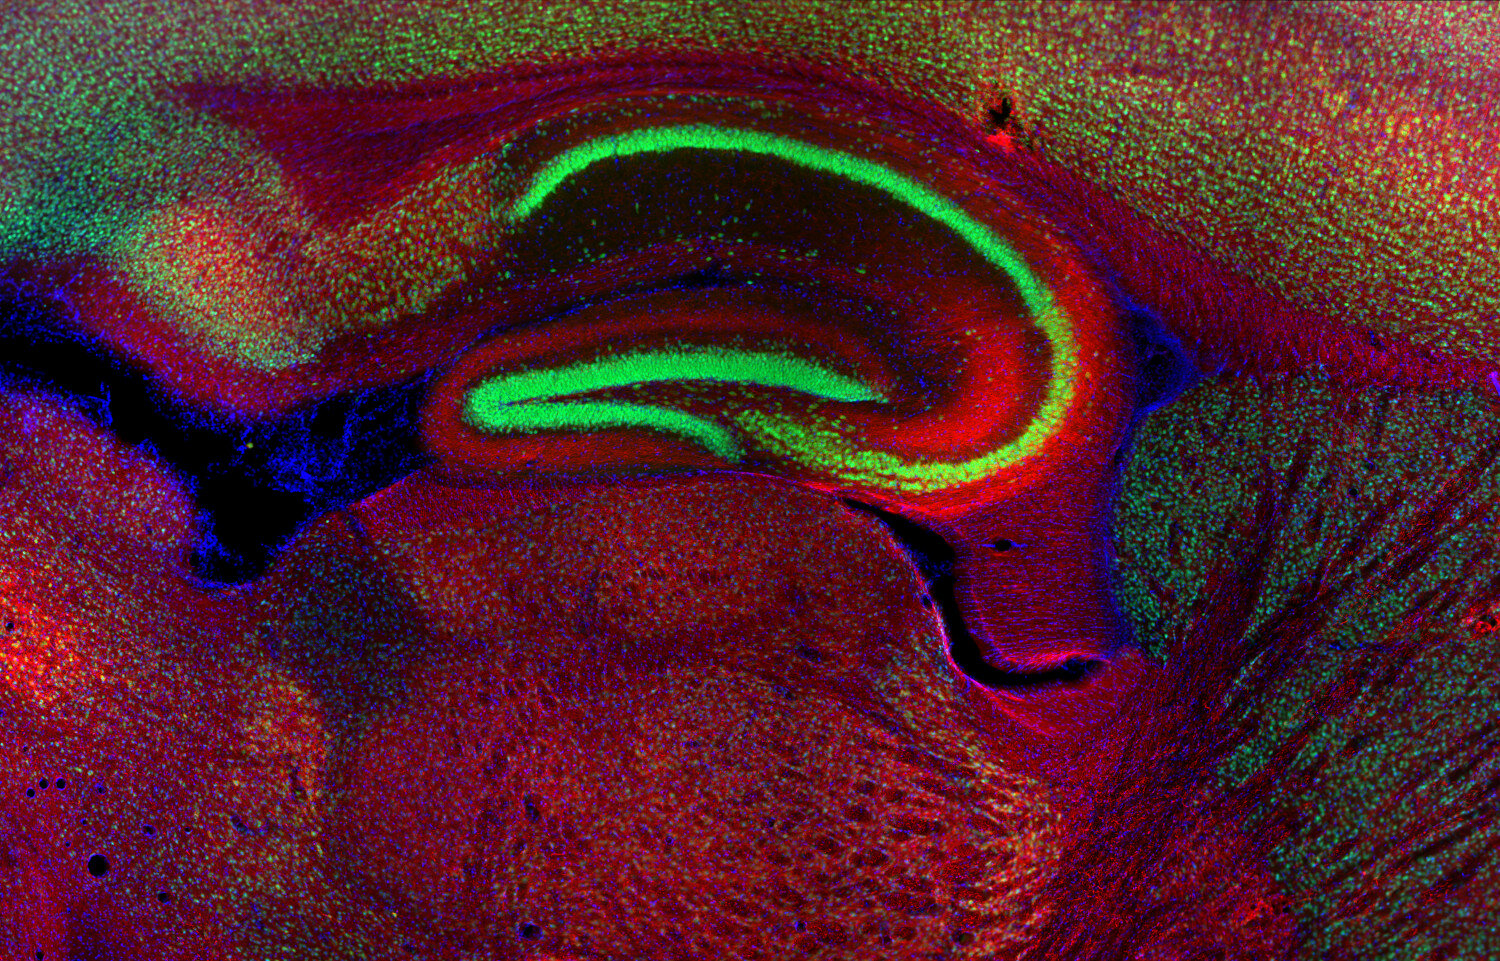

ICC: 1 : 500 gallery

Immunocytochemistry (ICC) on 4% PFA fixed cells. Immunoreactivity is usually revealed by fluorescence. Some antibodies require special fixation methods. For details, please refer to the “Remarks” section.

Immunohistochemistry (IHC) on 4% PFA perfusion fixed tissue with 24h PFA post fixation. Immunoreactivity is usually revealed by fluorescence or a chromogenic substrate. Some antibodies require special fixation methods or antigen retrieval steps. For details, please refer to the ”Remarks” section.